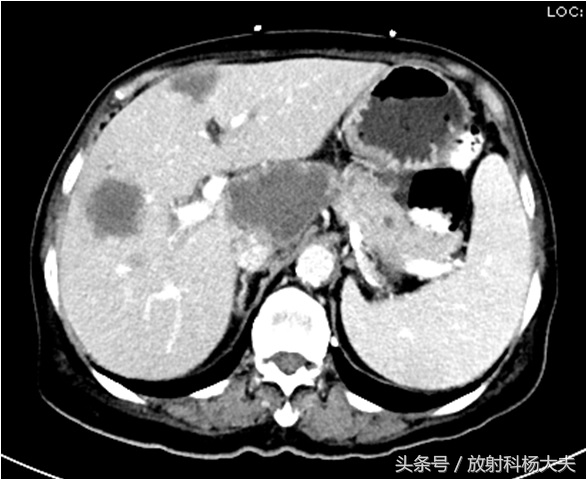

肝上的低密度,为肝转移瘤